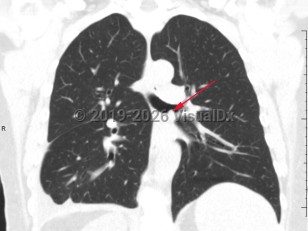

COVID-19